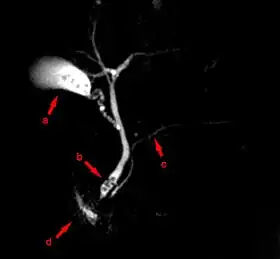

MRCP image showing stones in the distal common bile duct: (a) Gallbladder with stones, (b) Stones in bile duct, (c) Pancreatic duct, (d) Duodenum.

Magnetic resonance cholangiopancreatography (MRCP) is a medical imaging technique. It uses magnetic resonance imaging to visualize the biliary and pancreatic ducts non-invasively. This procedure can be used to determine whether gallstones are lodged in any of the ducts surrounding the gallbladder.